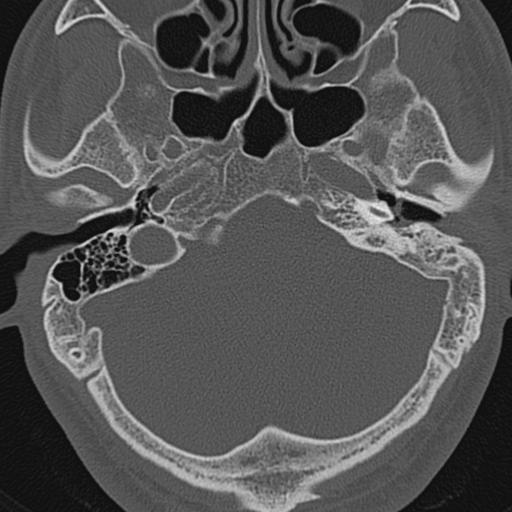

以下是引用zxl51642在2009-8-25 13:37:00的发言:[br]1、左侧慢性硬化型中耳乳突炎(中耳鼓室腔及听小骨受累),并胆脂瘤形成;2、左侧外耳道软组织密度影填塞,考虑炎性肉芽肿,建议结合临床;3、右侧颈静脉窝较左侧明显扩大,不排除颈静脉球瘤,建议mr进一步检查。

以下是引用随光逐影在2009-8-25 19:05:00的发言:[br]1)左侧慢性中耳乳突炎(肉芽肿或胆脂瘤形成),左侧外耳道炎性肉芽肿。2)右侧颈静脉球高位。